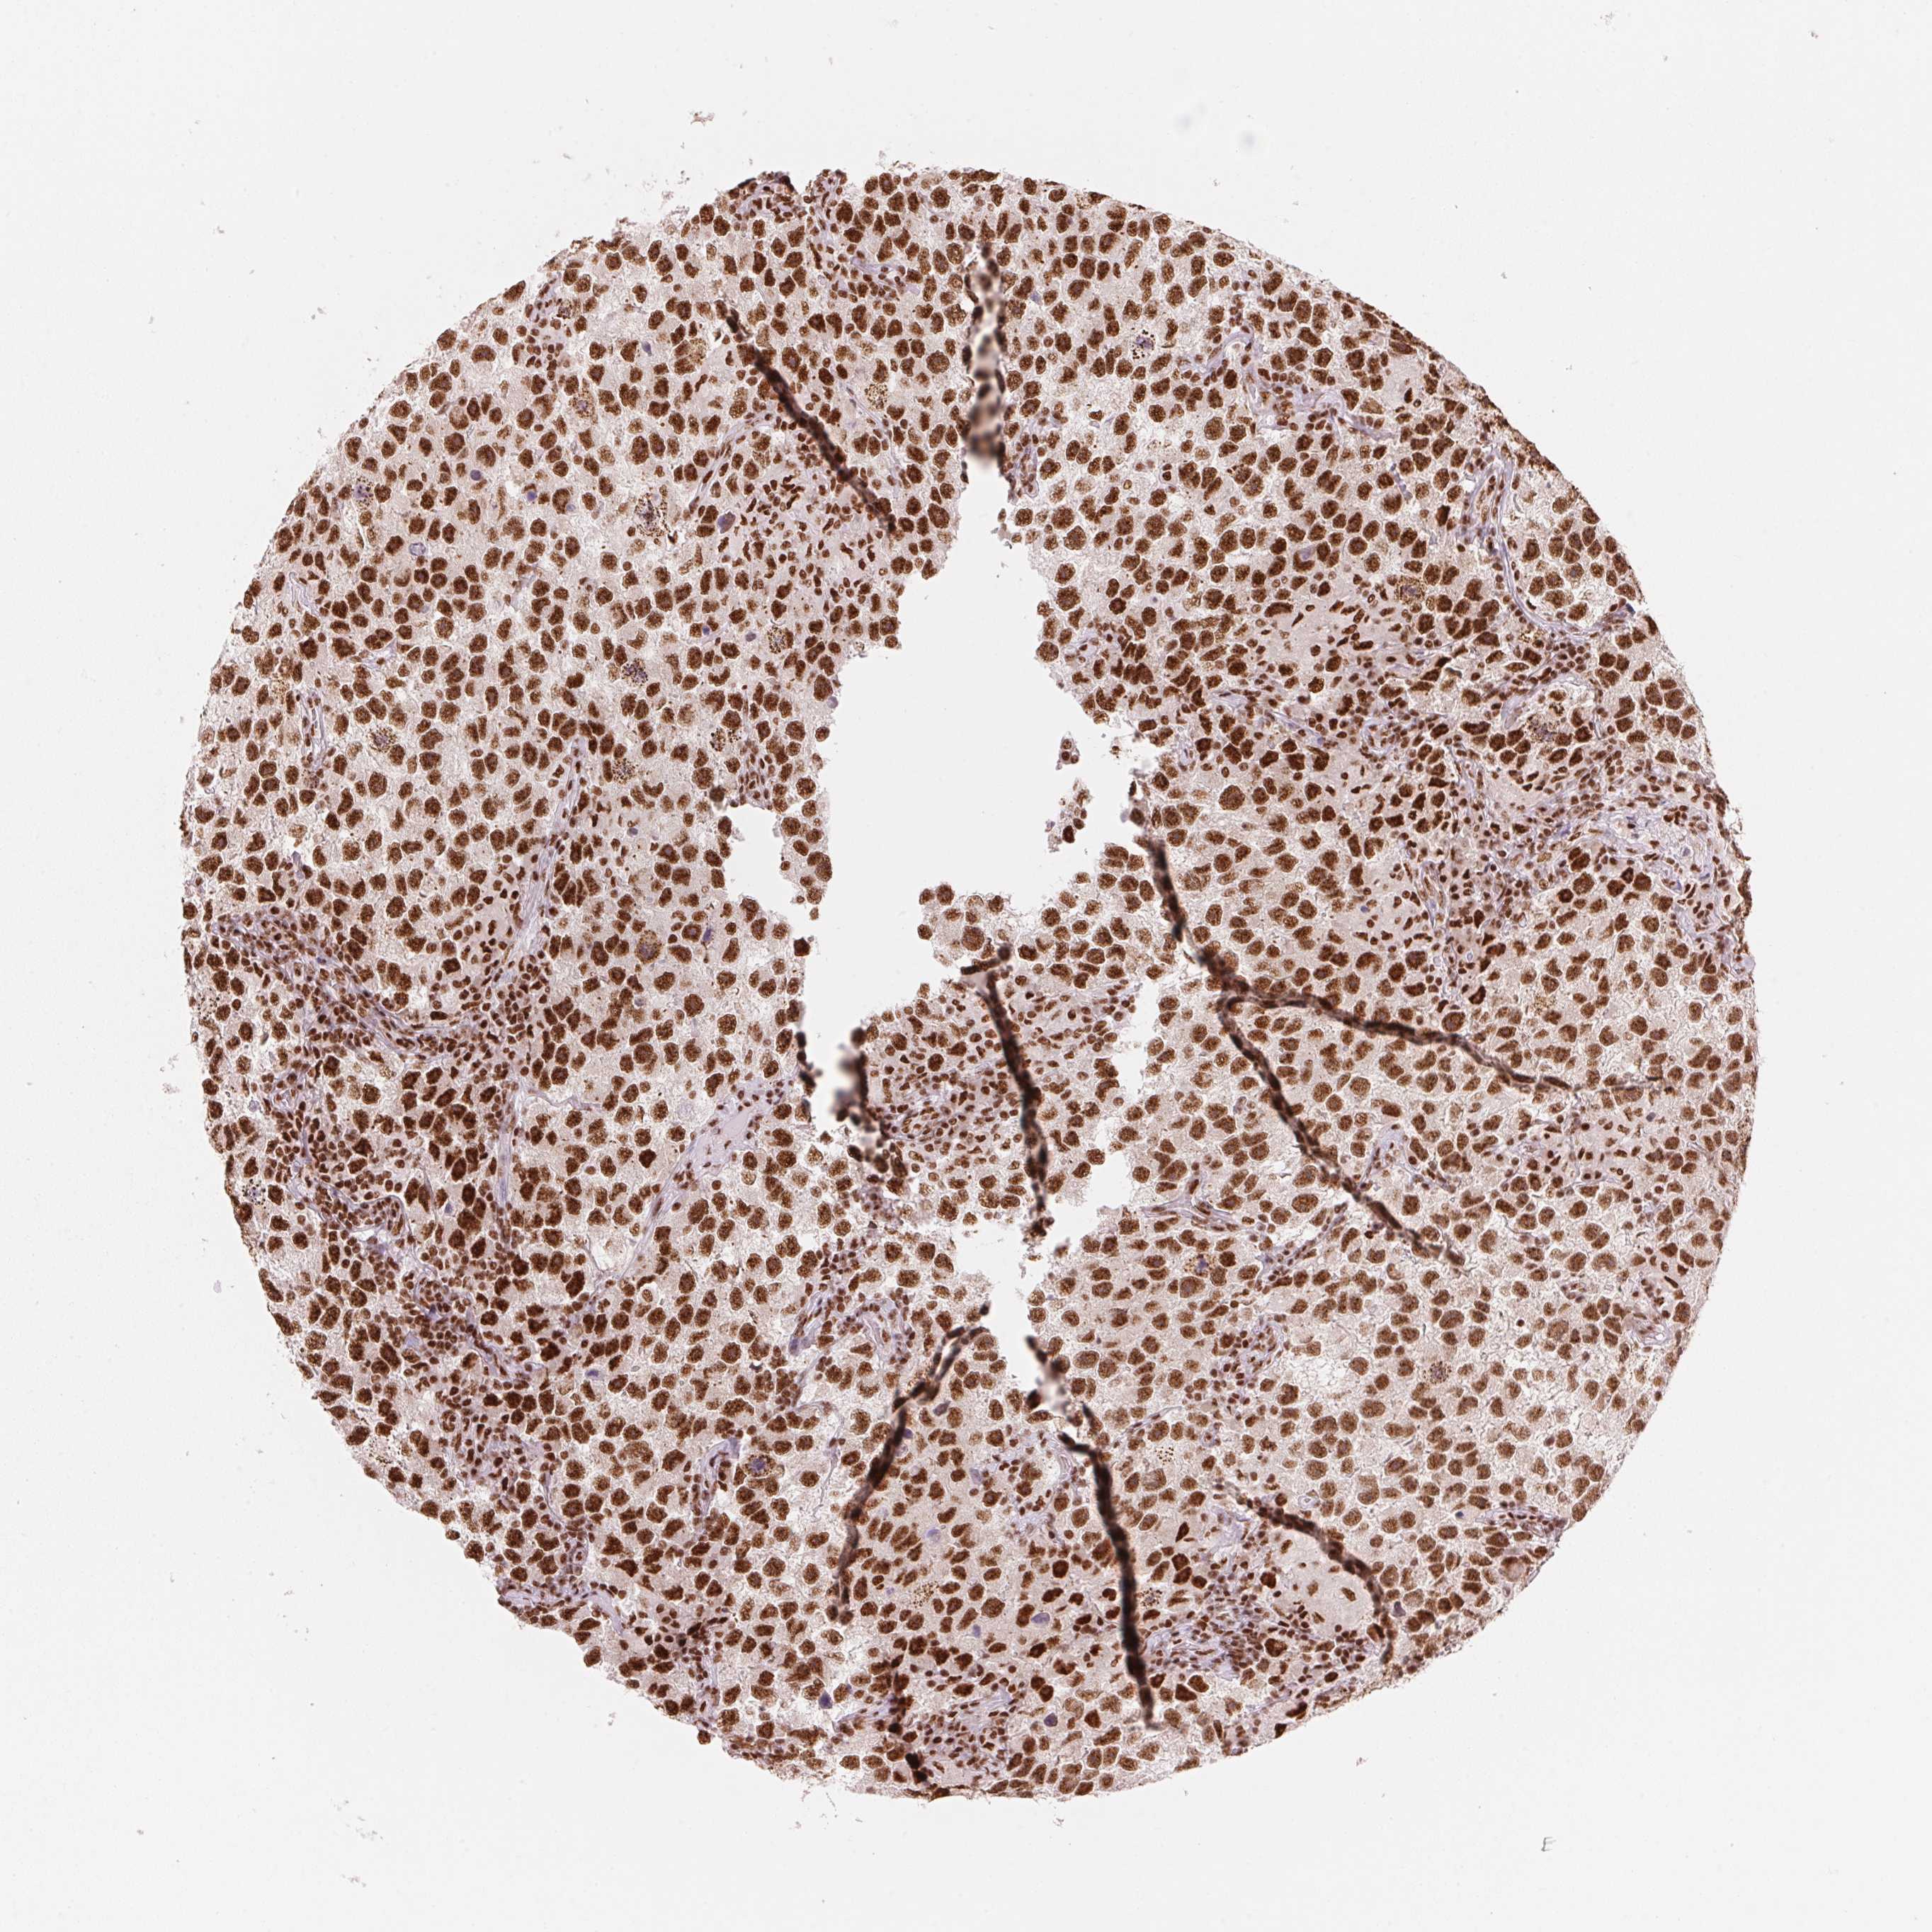

TESTIS CANCER - Protein expressioni

A mouse-over function shows sample information and annotation data. Click on an image to view it in a full screen mode. Samples can be filtered based on level of antibody staining by selecting one or several of the following categories: high, medium, low and not detected. The assay and annotation is described here.

Note that samples used for immunohistochemistry by the Human Protein Atlas do not correspond to samples in the TCGA dataset.

Antibody stainingi

Antibody staining in the annotated cell types in the current human tissue is reported as not detected, low, medium, or high, based on conventional immunohistochemistry profiling in selected tissues. This score is based on the combination of the staining intensity and fraction of stained cells.

Each image is clickable and will lead to virtual microscopy that enables deeper exploration of all samples and also displays staining intensity scores, fraction scores and subcellular localization as well as patient and tissue information for each sample.

Antibody HPA061593

Antibody CAB016327

Staining

High

Medium

Low

Not detected

Intensity

Strong

Moderate

Weak

Negative

Quantity

>75%

75%-25%

<25%

None

Location

Nuclear

Cytoplasmic/membranous

Cytoplasmic/membranous,nuclear

Seminoma, NOS

Carcinoma, Embryonal, NOS